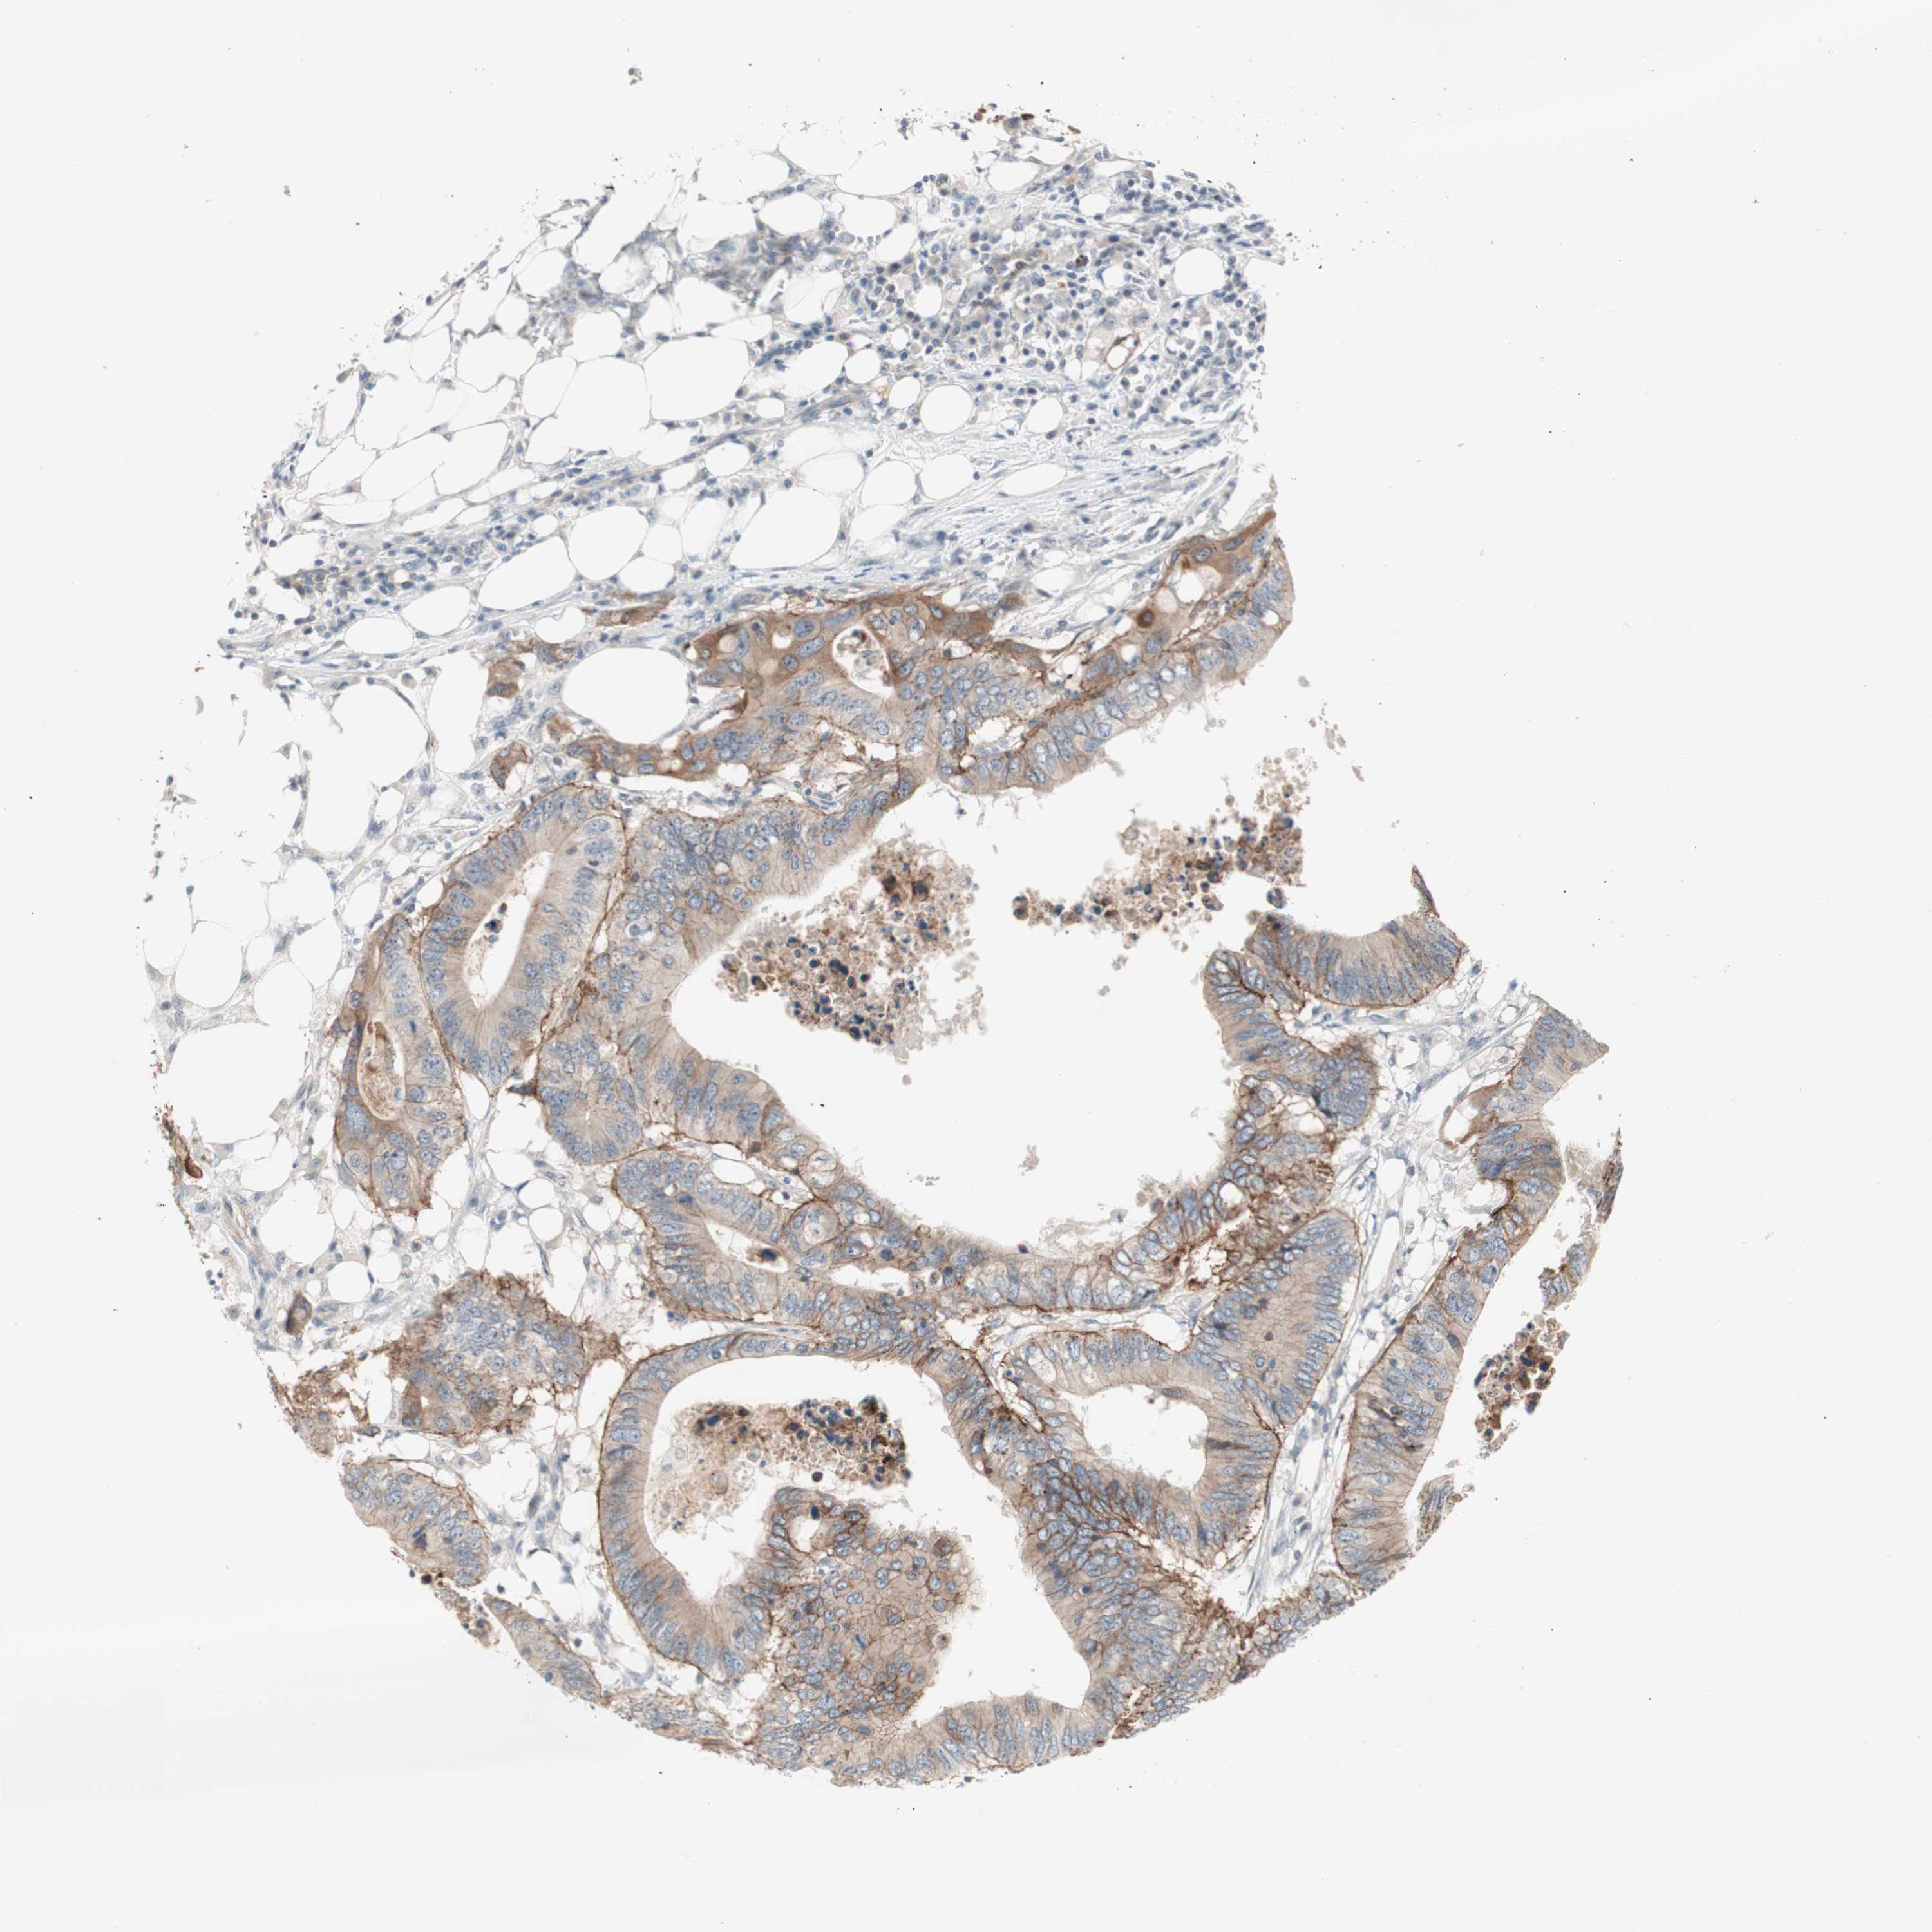

CANCER COLORECTAL CANCER Show tissue menu

Colorectal cancer

Human cancer

Colon adenocarcinoma